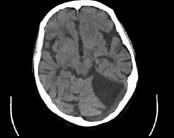

问题 患者因突发一侧肢体无力1天入院,行头颅MRI出现如图所示梗死,该病灶是下列哪两条血管供血区之间边缘带的局部缺血 ( )

选项 A、大脑中动脉和大脑前动脉 B、大脑后动脉和小脑上动脉 C、大脑中动脉的深穿支和大脑中动脉的皮层支 D、大脑中动脉和大脑后动脉 E、大脑前动脉和大脑后动脉

答案 D